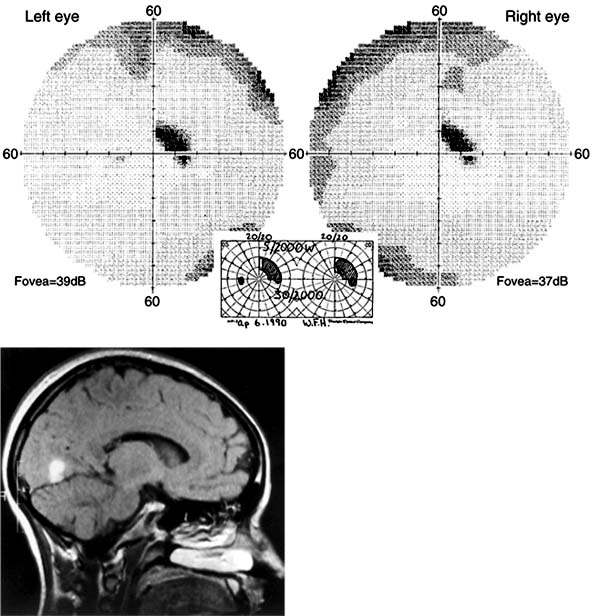

Figure 14-4

Figure 14-4: Occipital lobe abscess. Top: Automated perimetry and tangent screen examination showing homonymous, congruous, paracentral scotoma in right upper visual fields. Bottom: Parasagittal MRI showing lesion involving left inferior calcarine cortex. (Reproduced, with permission, from Horton JC, Hoyt WF: The representation of the visual field in human striate cortex. A revision of the classic Holmes map. Arch Ophthalmol 1991;109:816.)